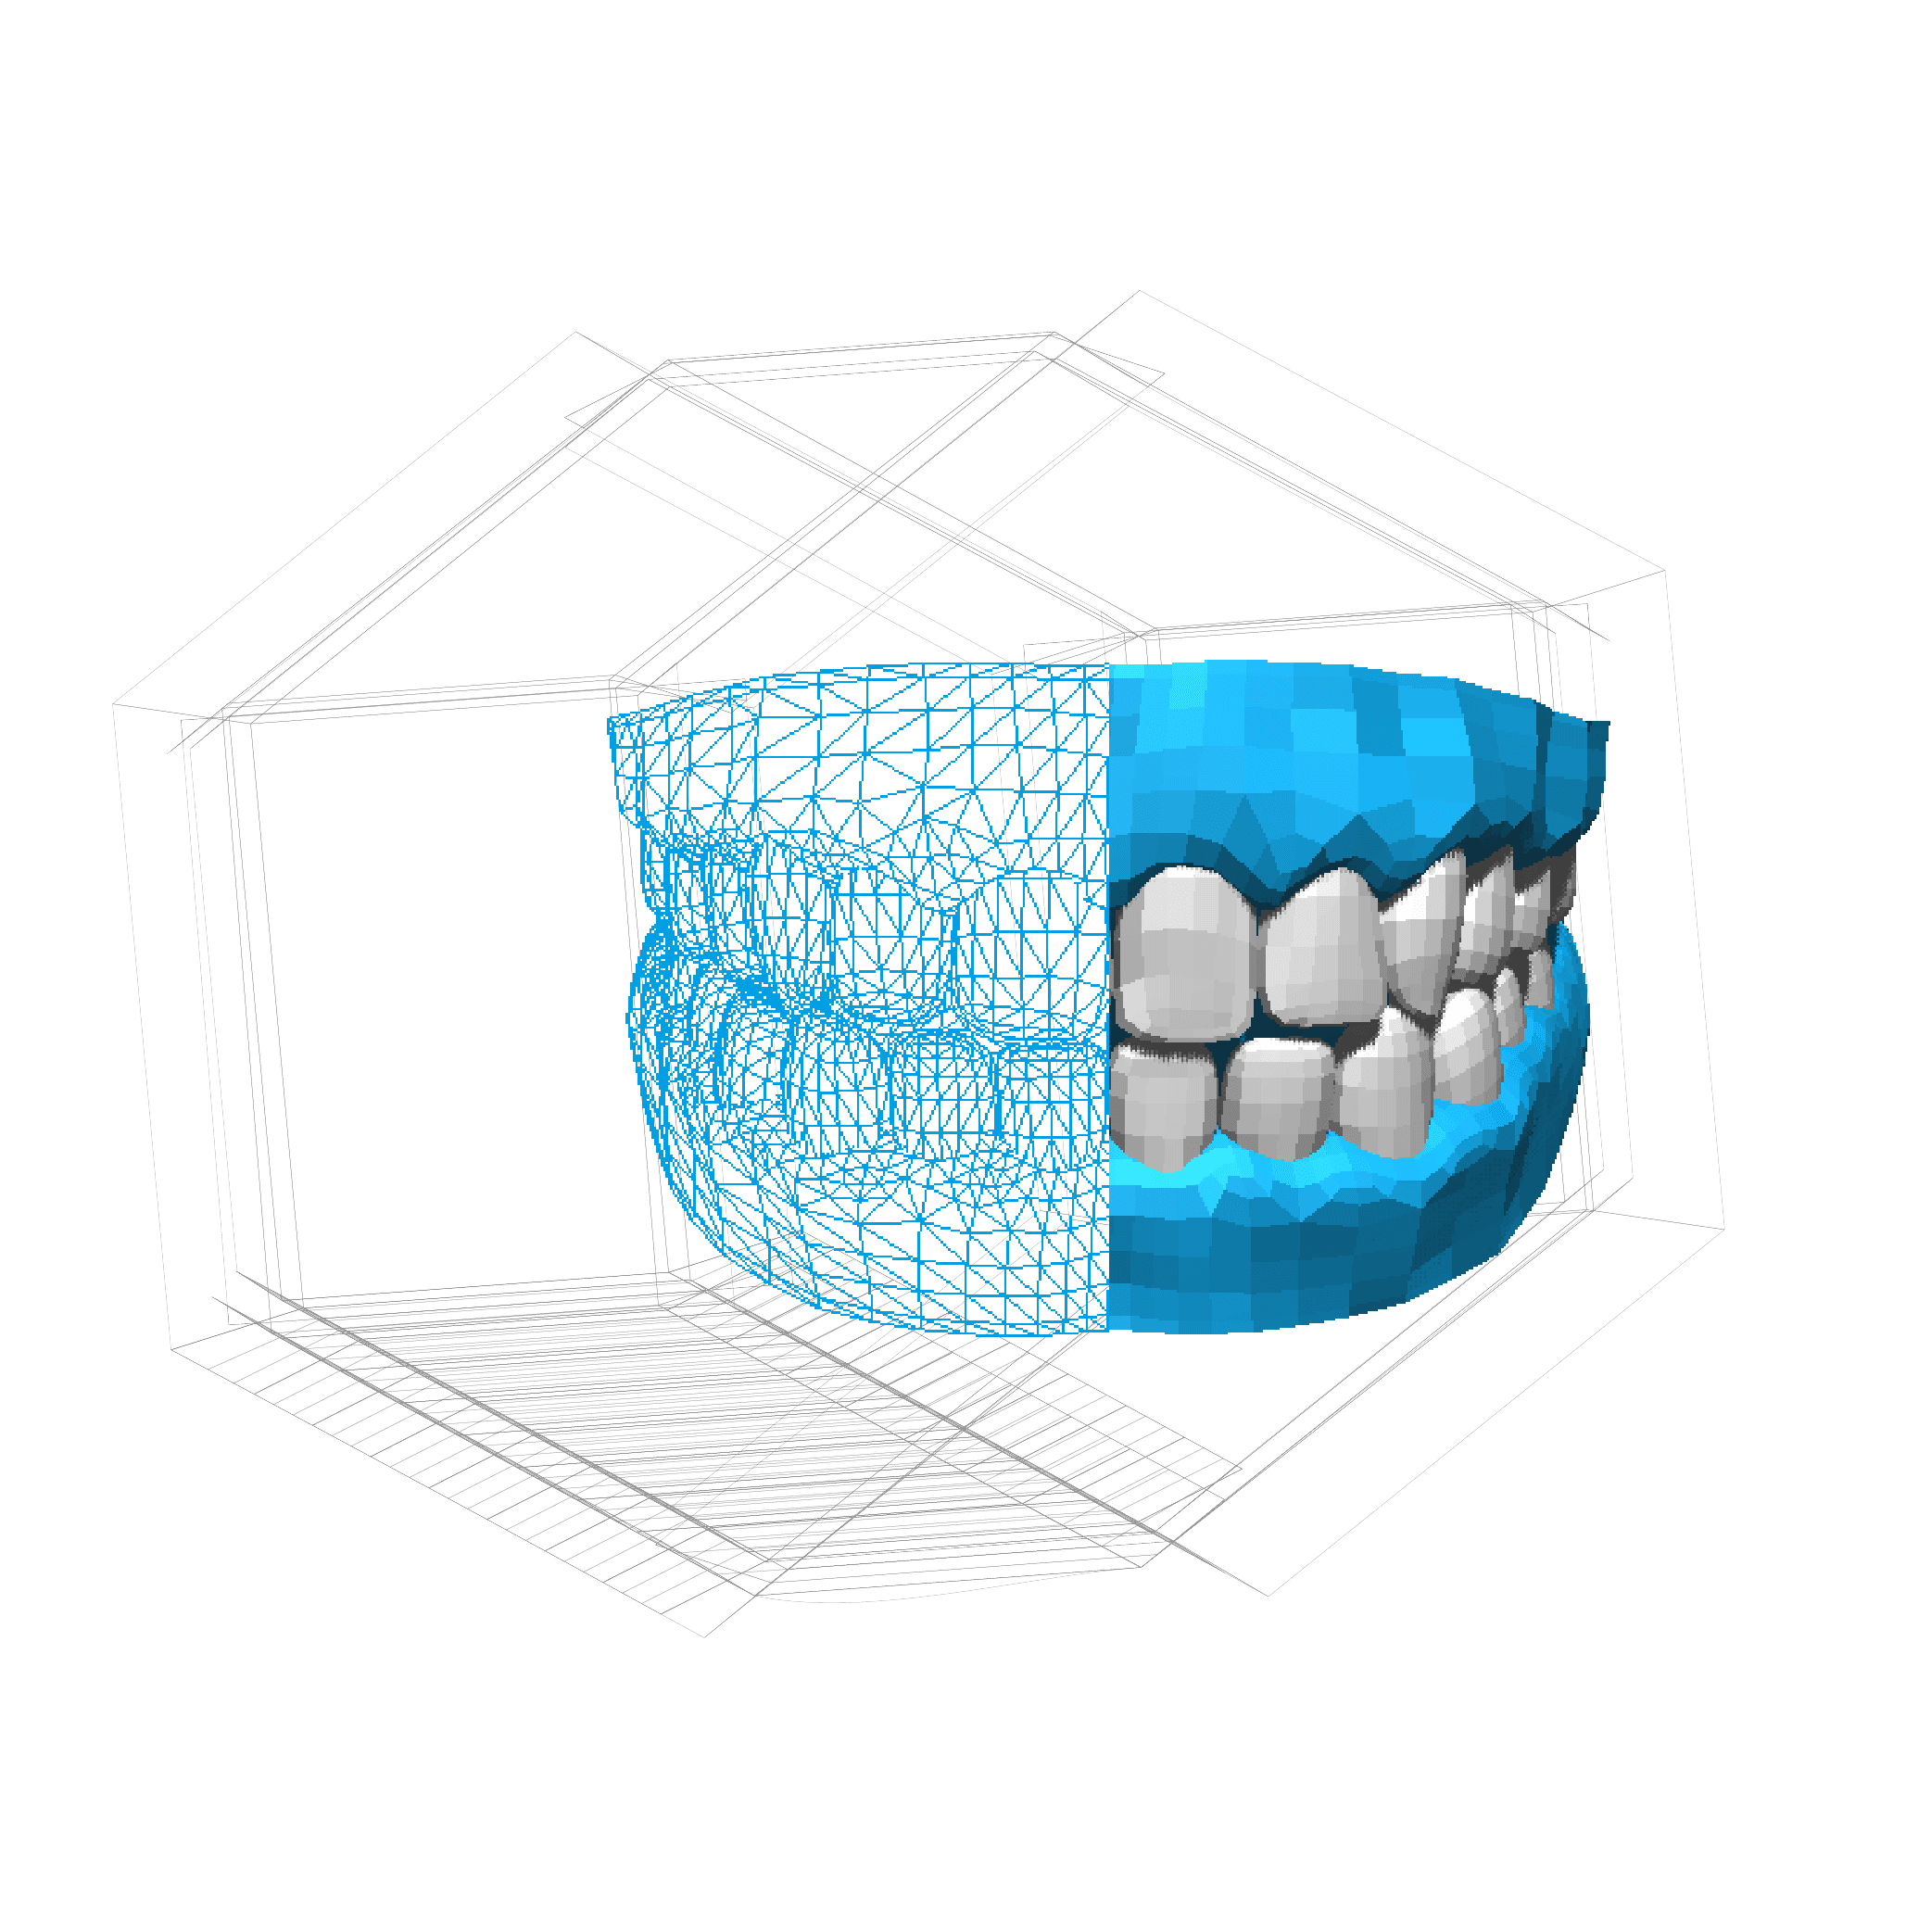

TDL SA, located in Massagno, Lugano, has been a leading dental laboratory since 1995, specializing in various dental aesthetic treatments and technologies. With a commitment to enhancing natural beauty, TDL SA employs advanced techniques and high-quality materials to ensure optimal results for their patients. Their offerings include CAD/CAM technology, orthodontics, and laser welding, reflecting their dedication to innovation in the dental field.